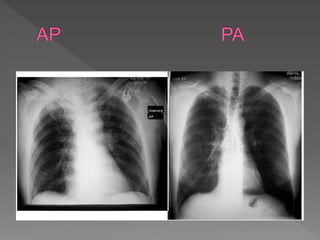

 Anterior - posterior (AP): This type of chest

X-Ray is generally less preferred because

the image of the heart and mediastinum is

less clear and focused in this projection.

 To obtain AP image, the patient is asked to

stand with their back against the film. If the

patient is unable to stand, an AP image can

also be taken with the patient sitting or

supine on the bed.

 A CXR taken in the radiology department is taken with the

patient standing erect in front of

 and facing the cassette containing the X-ray film.

 • The X-ray tube is positioned behind the patient hence the

X-rays pass from posterior to anterior

 (PA).

 • For patients confined to bed or chair, the PA technique is

not possible, therefore the X-ray film

 is placed behind the patient and the X-ray tube in front so

that the X-rays pass from anterior to

 posterior (AP).

 • In general, AP CXRs are taken with a shorter X-ray tube

to film distance compared to a PA film

 due to practical limitations.

 • There are marked differences in the CXR that can be attributed

entirely to the technique used.

 • The heart is an anterior organ in the chest and its size is

magnified on an AP view due to both

 the increase in divergence of the incident X-rays (the X-ray

source being closer to the film) and

 the increase in distance between the heart and the film when

compared to the PA technique. This

 magnification may make numerous mediastinal structures

appear abnormally enlarged.

 • On AP films, the clavicles cast a broader shadow and typically

overlay the apices making interpretation

 of these areas difficult (Fig 2.3).

 • In general, the AP film should be interpreted with caution.